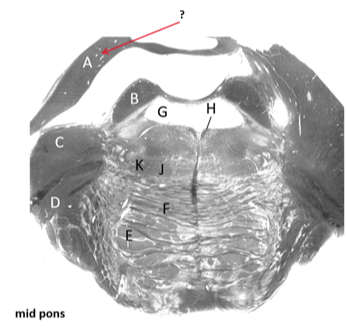

Name this and state its function.

Transverse pontine fibres.